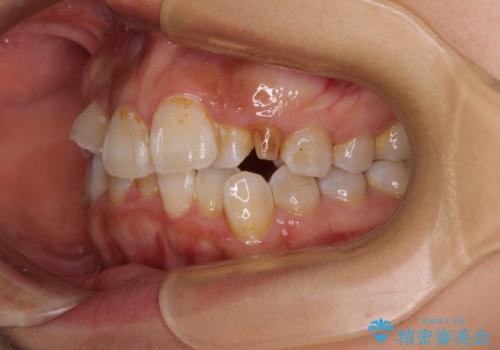

- 上下前歯のデコボコを気にして来院された患者様です。

上顎は両側の犬歯が骨内に埋伏しており、乳歯が残存している状態でした。

歯肉内に埋もれている場合には牽引することも可能ですが、両歯ともに骨内に完全に埋もれていたため、牽引することは不可能と判断しました。

口元の突出感があるわけではなく、叢生の程度もシビアではありませんでしたが、顎骨が小さく、左右ともに最後臼歯が歯肉に埋もれているため、下顎は左右第二小臼歯を抜歯することとしました。

上顎は左右ともに残存している乳歯を抜歯し、上下歯列を整えることとしました。